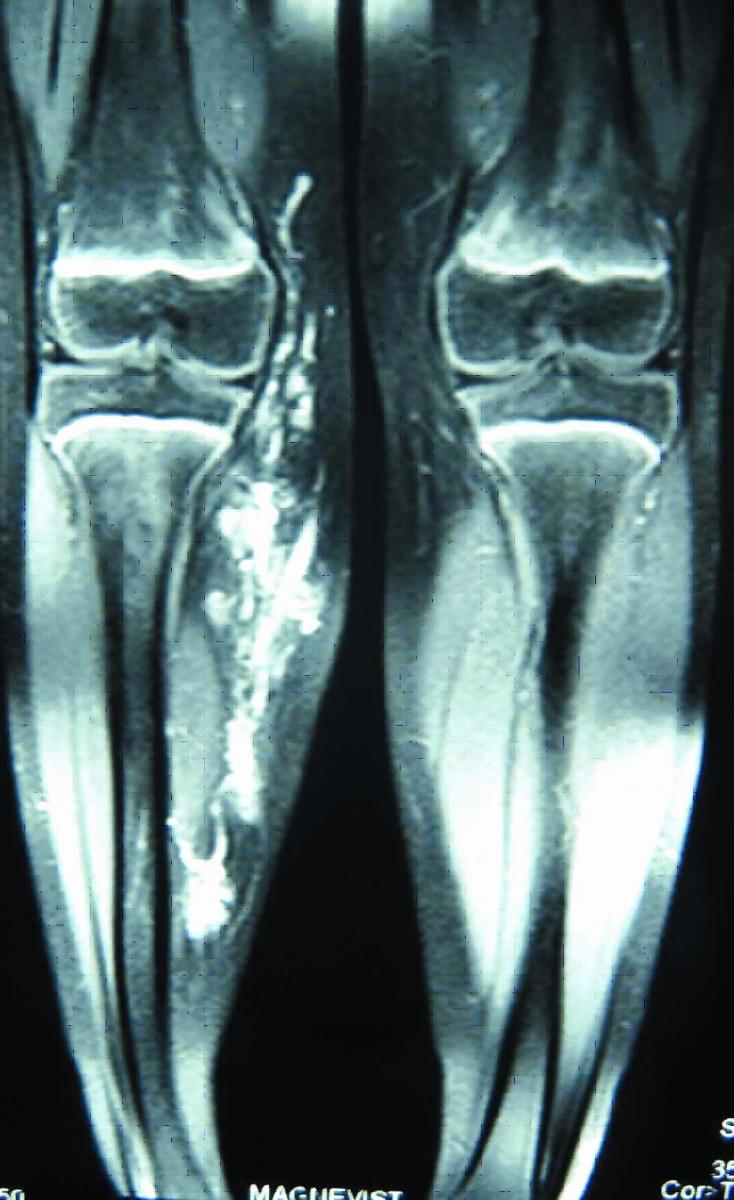

ภาพที่ 17. MRI ช่วยแสดงพยาธิสภาพการกระจายของโรคได้ชัดเจน.

การตรวจวินิจฉัยก้อนที่อยู่ลึก ควรใช้ MRI จะสามารถแสดงขนาดที่แท้จริงได้ดี เพราะก้อนสามารถ กระจายตัวไปทั้งระหว่างช่องว่างเนื้อเยื่อ หรือแทรกไปในเนื้อเยื่อได้. MRI สามารถแยกตำแหน่งของพยาธิสภาพออกจากเนื้อเยื่อปกติ ทำให้สามารถประเมินขอบเขตของรอยโรคก่อนการผ่าตัดได้ดีขึ้น (ภาพที่ 17).